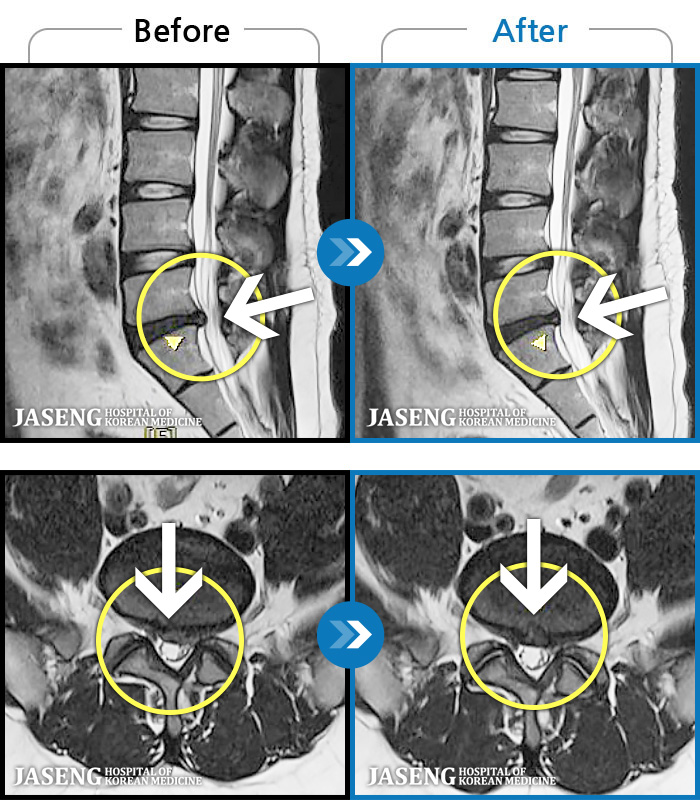

- MRI ġ

MRI ġ

1,245 MRI ũ ʸ Ȯϼ.

㸮 ϻ .